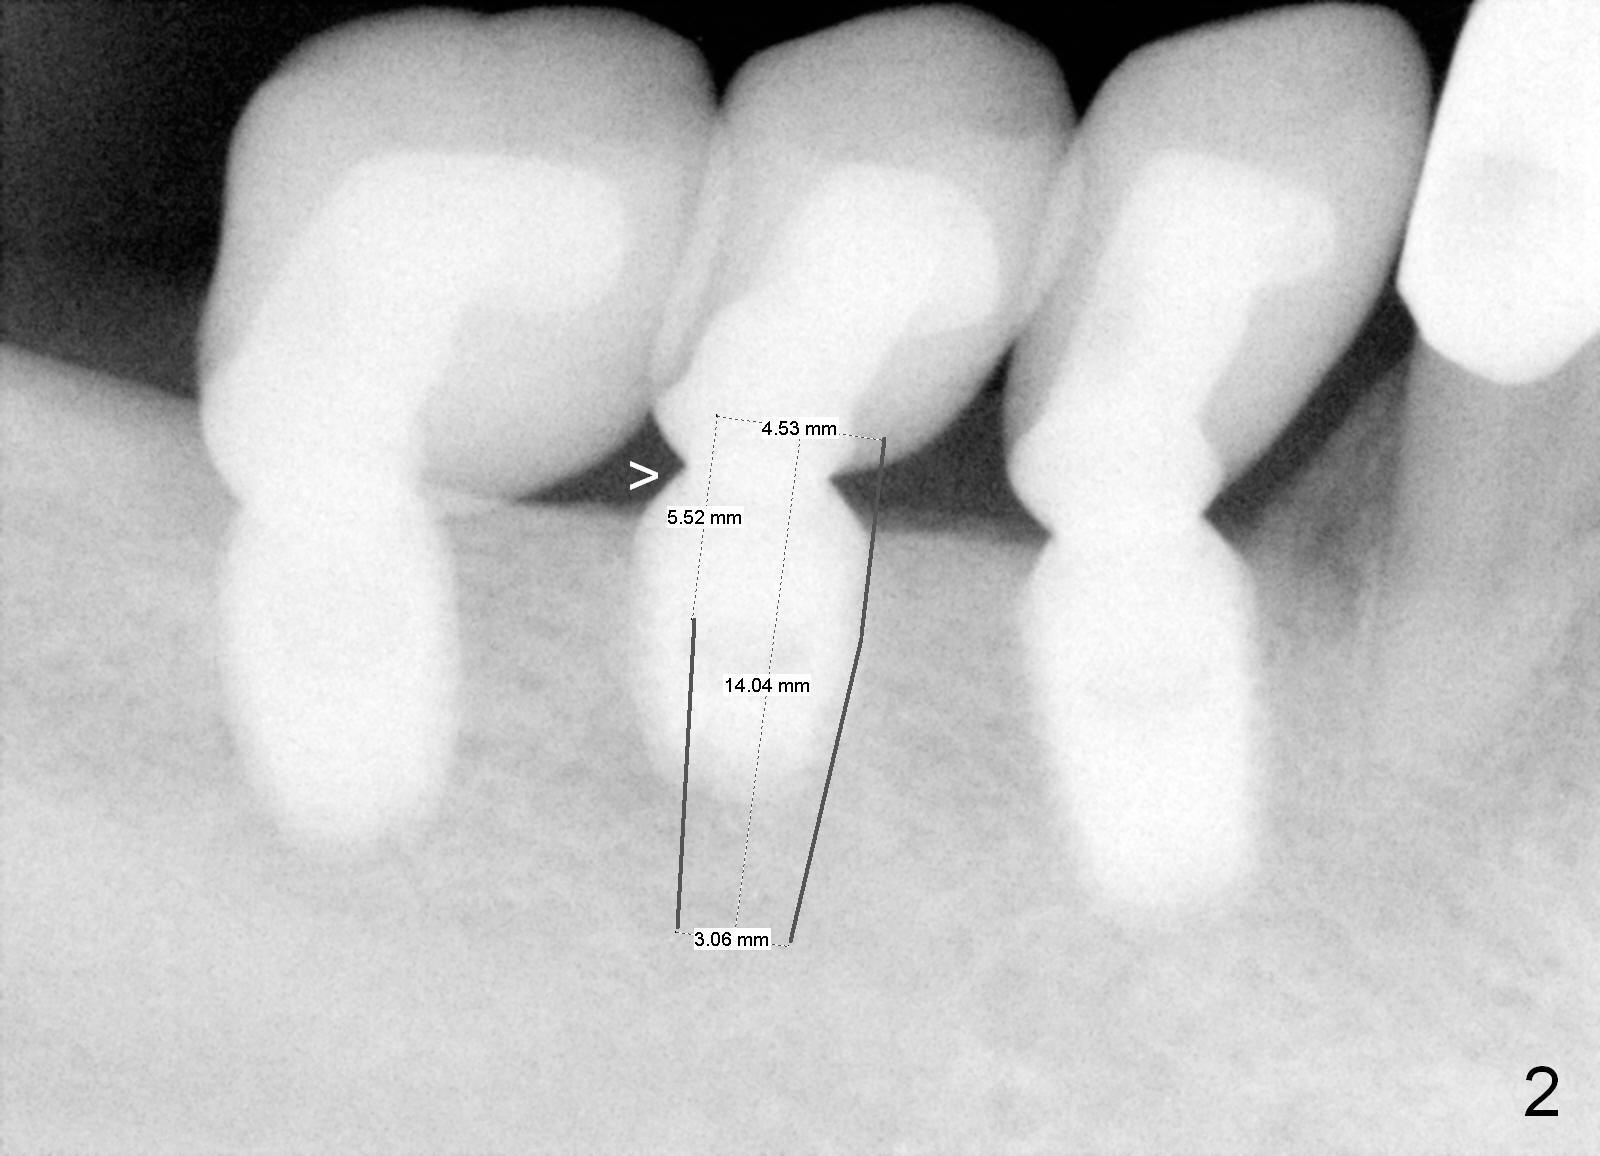

A 48-year-old man had 3 implants placed at #28-30 nearly 10 years ago (Fig.1). The implant at #29 is 4.5x6 mm because of proximity to the Mental Foramen. Bone shows gradual resorption around the implant at #29 two and 5 years postop (Fig. 2,3 >). It became loose when he accidentally bit on a piece of bone (Fig.4). A 4.5x11 (Fig.4) or 14 (Fig.2) mm tissue-level implant will be placed after Metronidazole treatment. CT will be taken tomorrow before surgery to further confirm the bone height. Since the previous implant was placed distally, the new one should be placed more mesially.